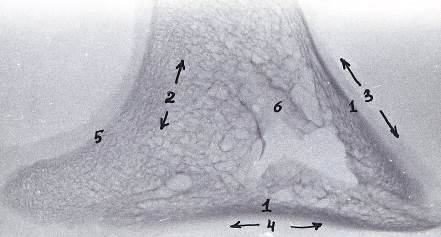

Рисунок 12 - Рентгенограмма шлифов копытцевой кости 3-го пальца грудной конечности теленка. Новорожденный

- компактное вещество, 2 - губчатое вещество, 3 - дорсальная стенка, 4 - подошвенная стенка, 5 - субхондральная кость суставного хряща, 6 - костные каналы сосудов